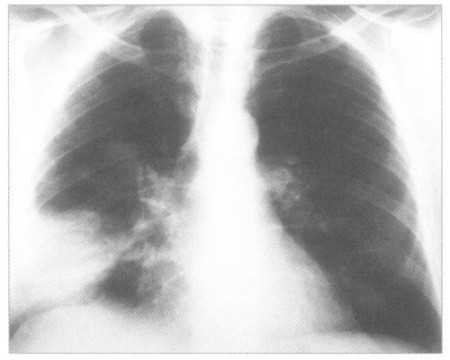

У Луцьку – спалах пневмонії

Останнім часом в літній період почастішали випадки легеневих захворювань, зокрема пневмонії.